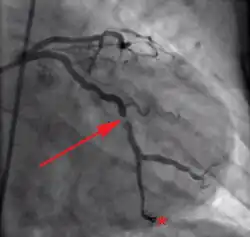

Der instabilen AP liegt in der Regel eine koronare Gefäßerkrankung und Arteriosklerose zugrunde. In diesem Rahmen kommt es zu einem lokalen Einriss von arteriosklerotischen Plaques in Koronararterien. Dies führt zu einer mechanischen Teilverlegung sowie reflektorischen Verengung der Arterien durch Vasospasmus. Ein sich bildender Thrombus kann einen akuten Myokardinfarkt auslösen.[15] Die Angina decubitus (auch Angina nocturna[18]) ist eine Form der instabilen Angina pectoris mit insbesondere nachts im Liegen auftretenden thorakalen Schmerzen. Ursache hierfür ist die Überlastung der vorgeschädigten Herzmuskulatur bei vermehrtem venösen Blutrückstrom im Liegen.[19]

Es ist notwendig, die Risikofaktoren für koronare Herzkrankheit zu minimieren (Tabakentwöhnung, Gewichtsreduktion, Blutfettkontrolle). Die Leitlinien empfehlen bei chronischer, stabiler Erkrankung prinzipiell Statine unabhängig von den Blutfettwerten, zudem vorbeugende Dauertherapie mit ASS und/oder anderen Gerinnungshemmern.[23] Zusätzlich können Betablocker verordnet werden.[24] Abhängig vom Schweregrad der Erkrankung kann ein Eingriff im Linksherzkatheterlabor erforderlich werden, bei dem Engstellen erweitert (PTCA) oder mit einem Stent versorgt werden. Wenn mehr als zwei Koronargefäße verengt sind oder der linke Hauptstamm, dann eignet sich meist eine Bypass-Operation besser.[24]